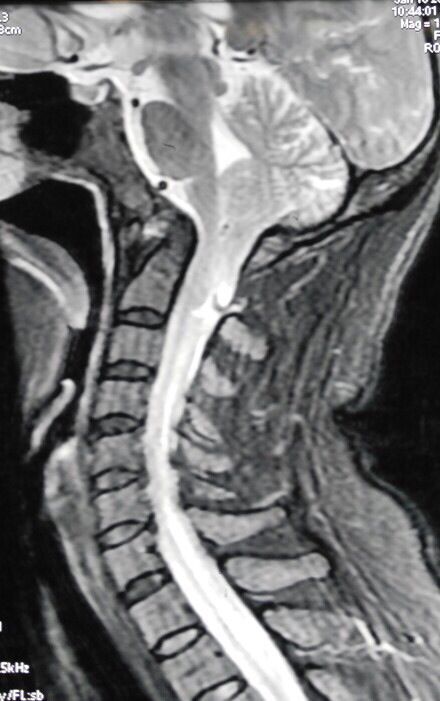

颈椎MRI,CT显示寰枢椎脱位,小脑扁桃体下疝,脊髓空洞